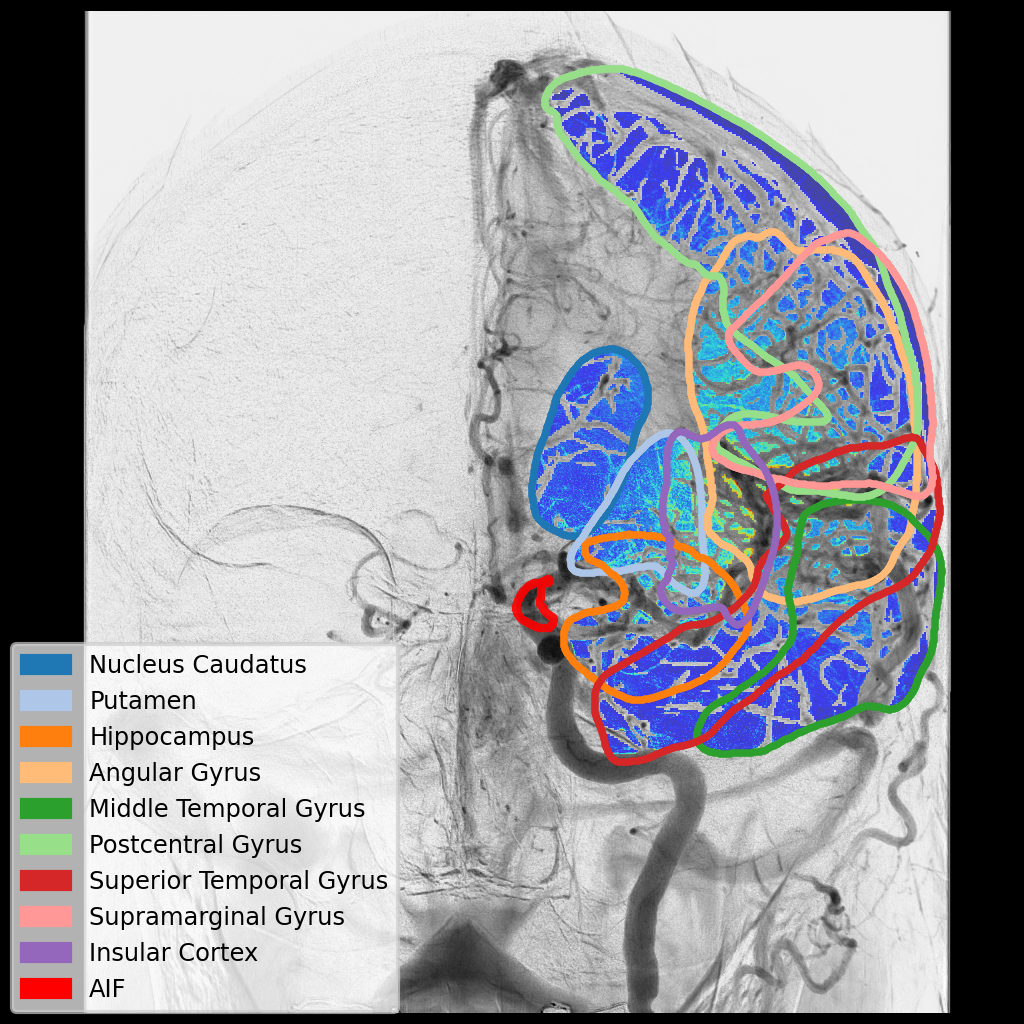

3. territory.jpg

P. M. van der Sluijs , L. Strong ,  F. G. te Nijenhuis , and 10 more authors

In Stroke Workshop on Imaging and Treatment CHallenges (SWITCH2025) , 2025

Within my PhD project, we are developing computer vision methods to automatically analyze cerebral Digital Subtraction Angiography (DSA) images. This includes automatic detection of vessel occlusions, quantifying vessel differences between the pre- and post-treatment DSA or delineating brain regions on DSA. The ultimate goal of these methods is to support clinical decision-making during mechanical thrombectomy procedures.